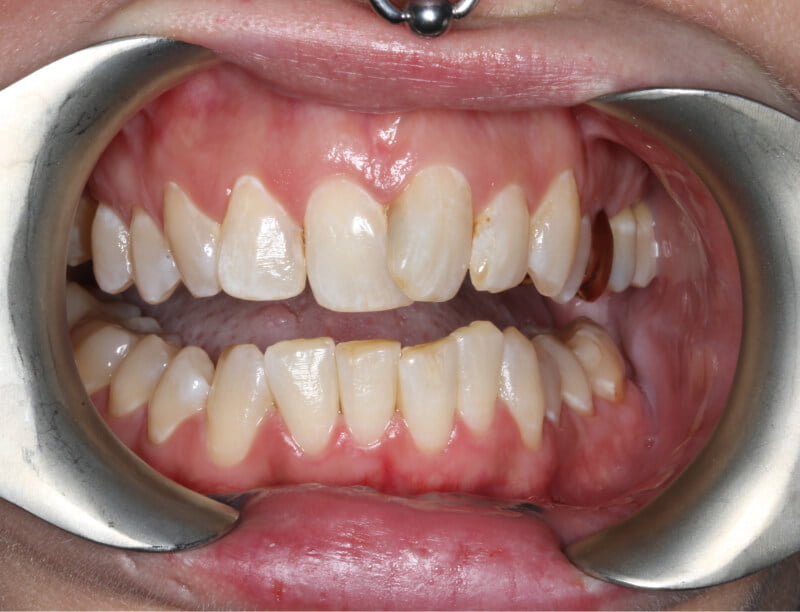

Crooked upper teeth with one of the front teeth overlapping the other. Difficulty in cleaning and preventing tooth decay.

Before